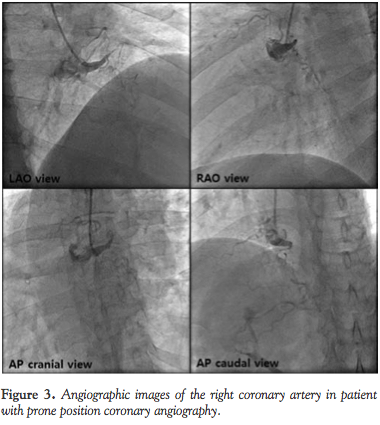

For further evaluation and proper perioperative risk assessment, we decided to undergo invasive coronary angiography. Since the patient suffered from intractable back pain, we gave him intravenous injection of meperidine hydrochloride, a potent opioid analgesic drug, prior to coronary angiography. However, the back pain was so severe, he could not lie down despite this treatment. Therefore, the position of the patient was changed from supine position into prone position, and consequently, he was able to undergo coronary angiography by left transradial approach (Figure 2). Coronary angiography with a 5 Fr Judkins right

catheter revealed total occlusion of the proximal RCA (Figure 3). Coronary angiography with a 5 Fr Judkins left catheter revealed diffuse 50%-60% luminal narrowing of the proximal to distal left anterior descending coronary artery (LAD) and total occlusion of the proximal left circumflex coronary artery (LCX) with collateral flows from distal LAD and septal branches to posterior descending and posterolateral branches of the RCA (Figure 4).

In our case, prone position coronary angiography was performed without difficulty. In addition, interpretation of prone position coronary angiography was simply done since only the cranial and caudal views were opposite compared to conventional supine position angiography. These consequences may be due to the geometry of the heart as well as the coronary anatomy, which were neither parallel nor perpendicular to the patient’s position. Although we did not undergo percutaneous coronary intervention (PCI) since it was not feasible to achieve complete revascularization, performing prone position PCI would not be troublesome compared to conventional supine position PCI.